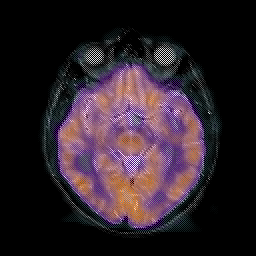

AIDS dementia: overlay -- Slice #7

[Home][Help][Clinical][Tour 1] Slice 7